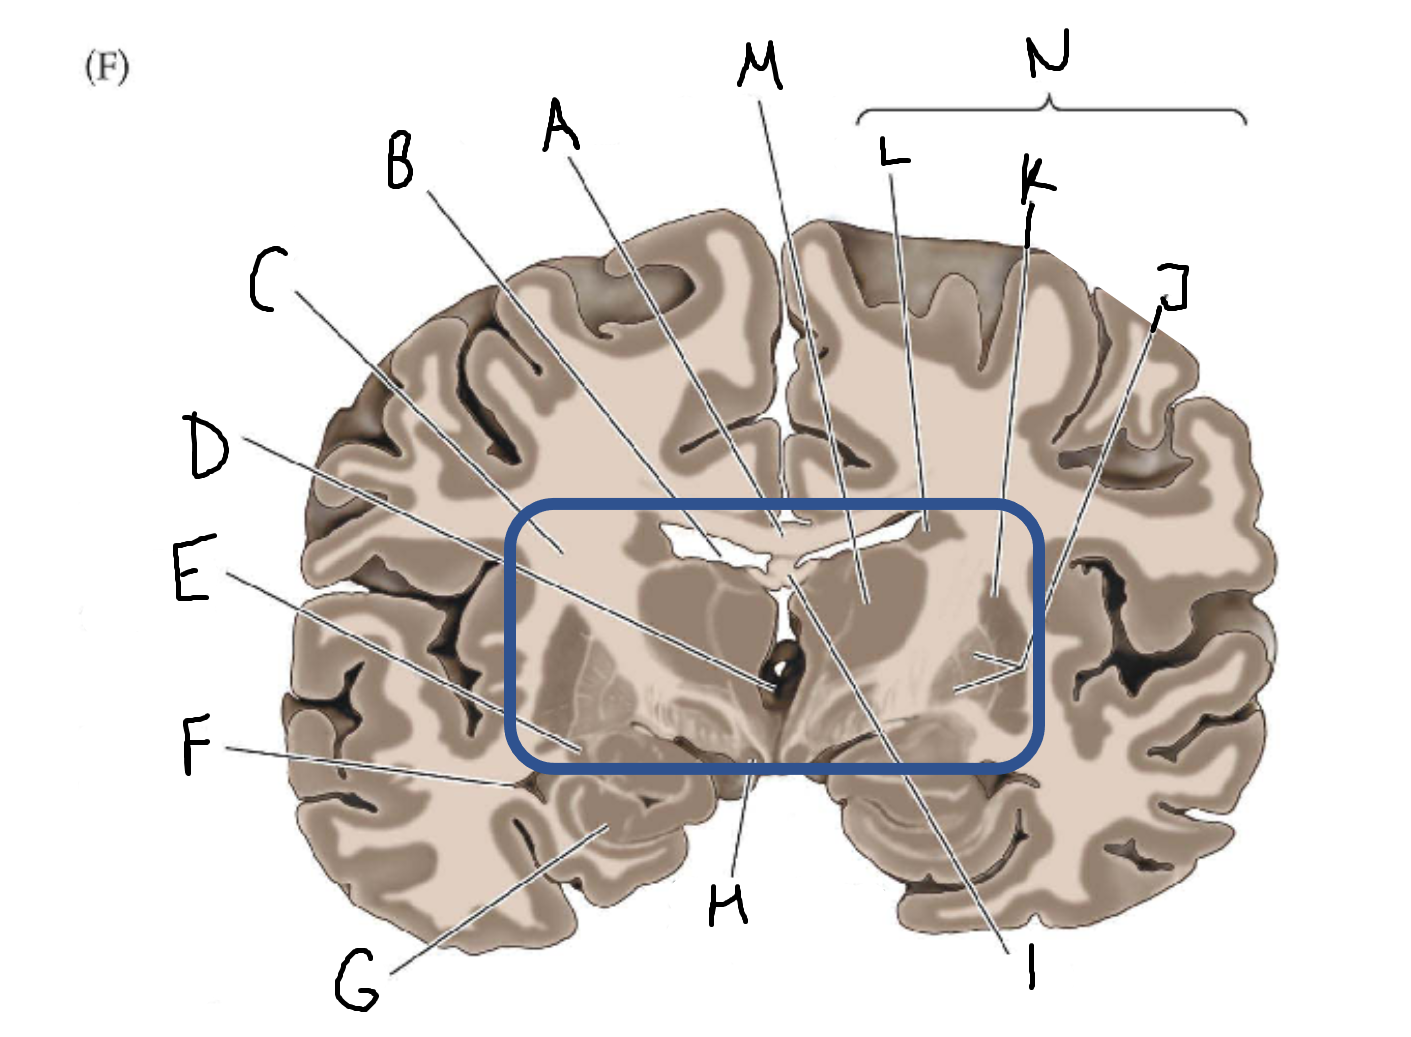

A

corpus callosum

B

lateral ventricle

C

internal capsule

D

third ventricle

E

tail of caudate nucleus

F

lateral ventricle

G

hippocampus

H

mammillary body

I

fornix

J

globus pallidus

K

putamen

L

caudate

M

thalamus

N

basal ganglia